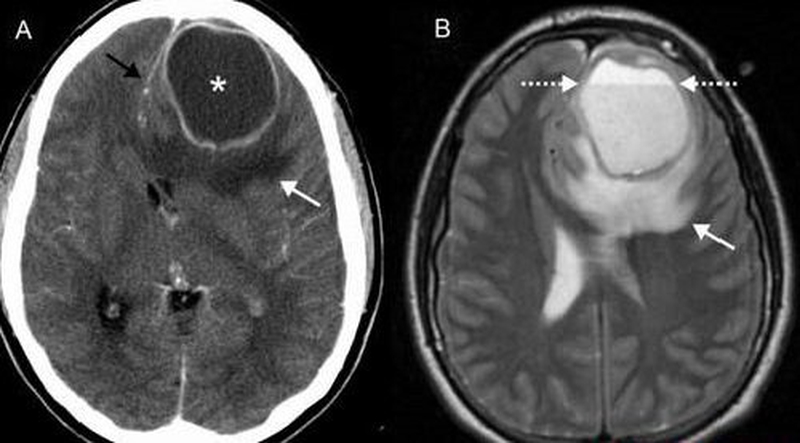

Áp xe ngoài màng cứng là sự tích tụ mủ giữa màng cứng và hộp sọ. Các triệu chứng của áp xe ngoài màng cứng bao gồm sốt, đau đầu, nôn, mệt mỏi, thiếu sót thần kinh khu trú, động kinh và/hoặc hôn mê.

Áp xe ngoài màng cứng là một bệnh hiếm gặp do nhiễm trùng ở vùng giữa xương sọ hoặc cột sống và màng (màng não) bao phủ não và tủy sống. Nếu nhiễm trùng này nằm trong khu vực của hộp sọ, nó được gọi là áp xe ngoài màng cứng nội sọ. Nếu nó được tìm thấy ở khu vực cột sống, nó được gọi là áp xe ngoài màng cứng tủy sống. Phần lớn nằm ở cột sống.

Khi đến các cơ sở y tế, bạn sẽ được các bác sĩ chỉ định thực hiện khám sức khỏe để tìm kiếm tình trạng mất chức năng, chẳng hạn như cử động hoặc cảm giác. Cụ thể: